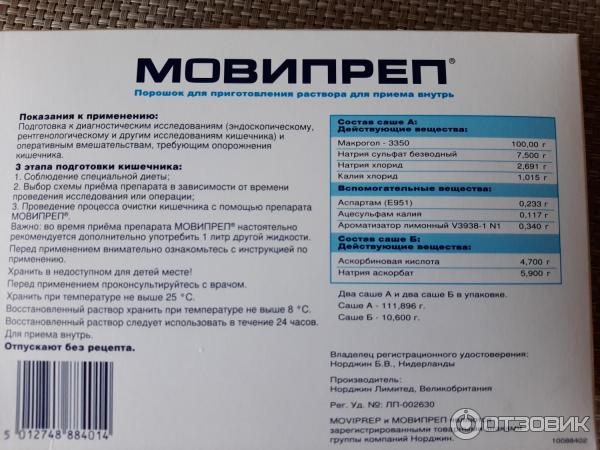

Подготовка к ирригоскопии: необходимые препараты